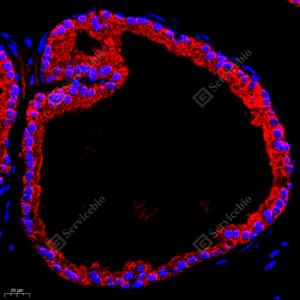

IF检测RAP2C蛋白(货号 GB112424)(红色). 样品: 小鼠膀胱, 4%多聚甲醛 (货号G1101) 固定12-24小时. 抗原修复: Tris-EDTA抗原修复液(pH 9.0) (G1203), 98℃, 20分钟. 封闭: 3% BSA(货号GC305010)的PBS溶液, 室温孵育30分钟. —抗: 1: 700稀释, 4℃ 孵育过夜. 二抗: Cy3标记山羊抗兔IgG (H+L) (货号GB21303), 1: 300稀释, 室温孵育1小时. |